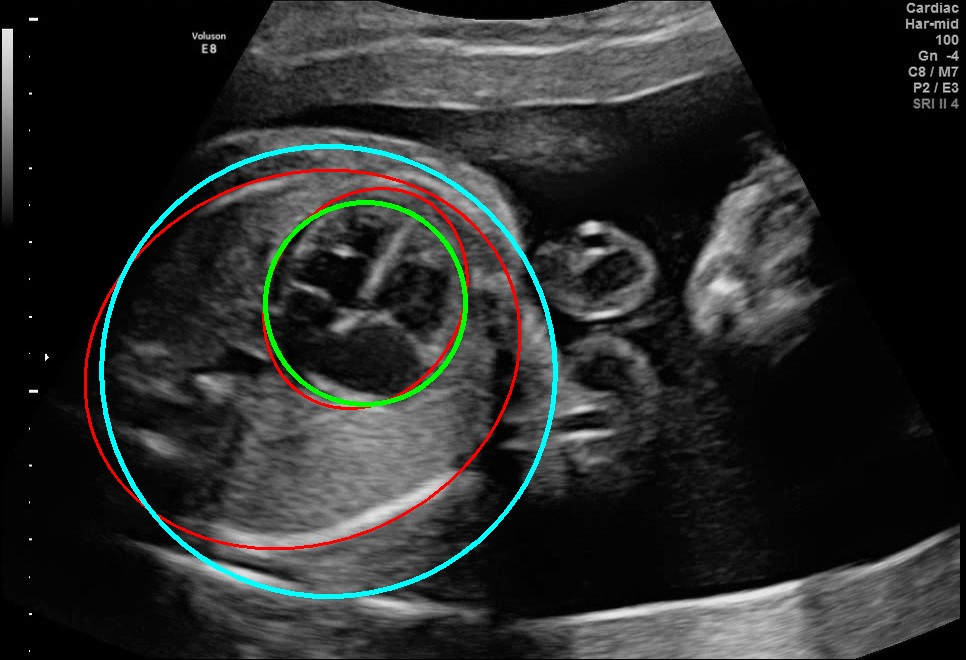

Results of ablation study.

As shown in Fig. 3 , both the proposed ellipse regression loss and IoU loss are necessary for ellipse detection. If the EllipseNet only supervised by IoU loss (first column), the model fails to optimize the major and minor axis separately, and the predicted ellipses degenerate into circles like the CircleNet. It is clear that the supervision of IoU loss can help to improve the prediction of location and shape (first and second row) and to correct the angle (last row).